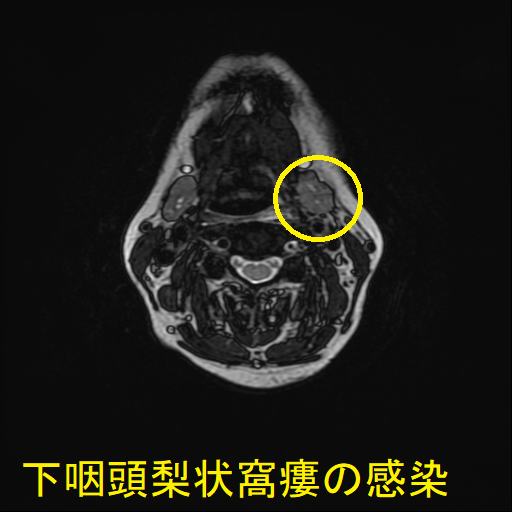

- 通常の造影頸部CTで、甲状腺外の膿瘍形成と、その範囲が明らかになります。

- 下咽頭部造影CTで、下咽頭梨状窩瘻を見つけます。

急性化膿性甲状腺炎に至らない下咽頭梨状窩瘻の感染もあります。下咽頭梨状窩瘻が甲状腺内でなく、甲状腺周囲に開口している場合に起こります。